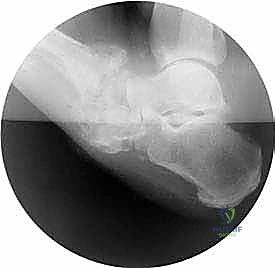

- المرحلة الأولى (مرحلة التطور والتفتت): تدمير حاد. تظهر الأشعة تفتت العظام، خلع المفاصل، وتكون شظايا عظمية. القدم تكون حمراء، ساخنة، ومتورمة بشدة.

- المرحلة الثانية (مرحلة الالتحام - Coalescence): يبدأ الجسم في محاولة إصلاح الضرر. يقل التورم والحرارة، وتبدأ الشظايا العظمية في الاندماج العشوائي.

- المرحلة الثالثة (مرحلة التصلب وإعادة البناء): تبرد القدم وتستقر، لكنها تلتئم على وضع مشوه بشدة (قدم الروكر)، مما يمهد الطريق للتقرحات المستعصية.